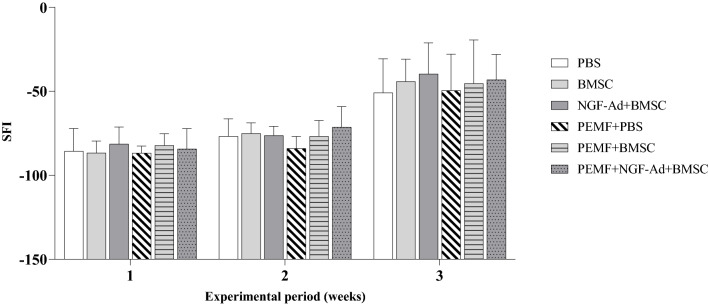

Figure 3 shows the overall changes of SFI. One week after the crush injury, SFI was around -90 due to the loss of function induced by the nerve damage. A gradual increase in SFI was observed during the following 2 weeks. However, there were no statistical differences between the groups, except for the PEMF and PEMF + NGF-Ad + BMSC group (− 82.94 ± 7.24 and -71.34 ± 12.27, respectively, p = 0.0173) at 2 weeks post-operatively.

Fig. 3.

Graph of weekly sciatic function index (SFI). Gradual increase of SFI was observed from 1 week postoperatively. The PEMF + NGF-Ad + BMSC group showed higher SFI than PEMF group at 2 weeks post-operatively (p = 0.0173, Fisher’s protected least significant difference test). Otherwise, no statistical differences were found among groups during 3 weeks